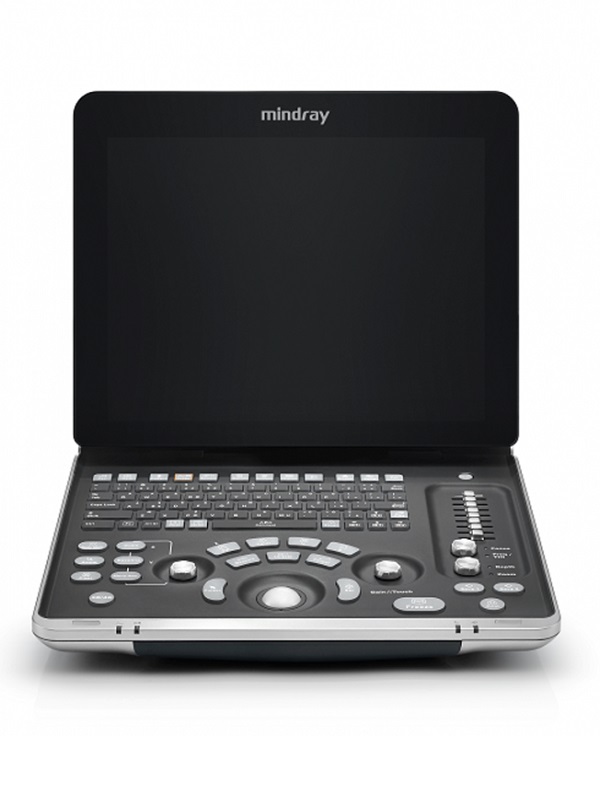

Mindray Z60 – Diagnostic Ultrasound System

Mindray Z60 is a wise choice for those who require high-quality image performance, ease of mobility, as well as affordability when it comes to advanced ultrasound imaging

Mindray Z60 – Diagnostic Ultrasound System

Mindray Z60 is a wise choice for those who require high-quality image performance, ease of mobility, as well as affordability when it comes to advanced ultrasound imaging. With comprehensive configurations and an integrated design, the Z60 is the result of Mindray’s continuous and determined efforts towards making primary healthcare more efficient, effective and accessible for all.

Ergonomics

·Integrated design with internal AC power adapter

15 inch full screen design

60 degree tilting angle adjustable monitor

Max 3 universal transducer connectors

500GB hard disk for large patient data storage

- 1.5h scanning with rechargeable battery